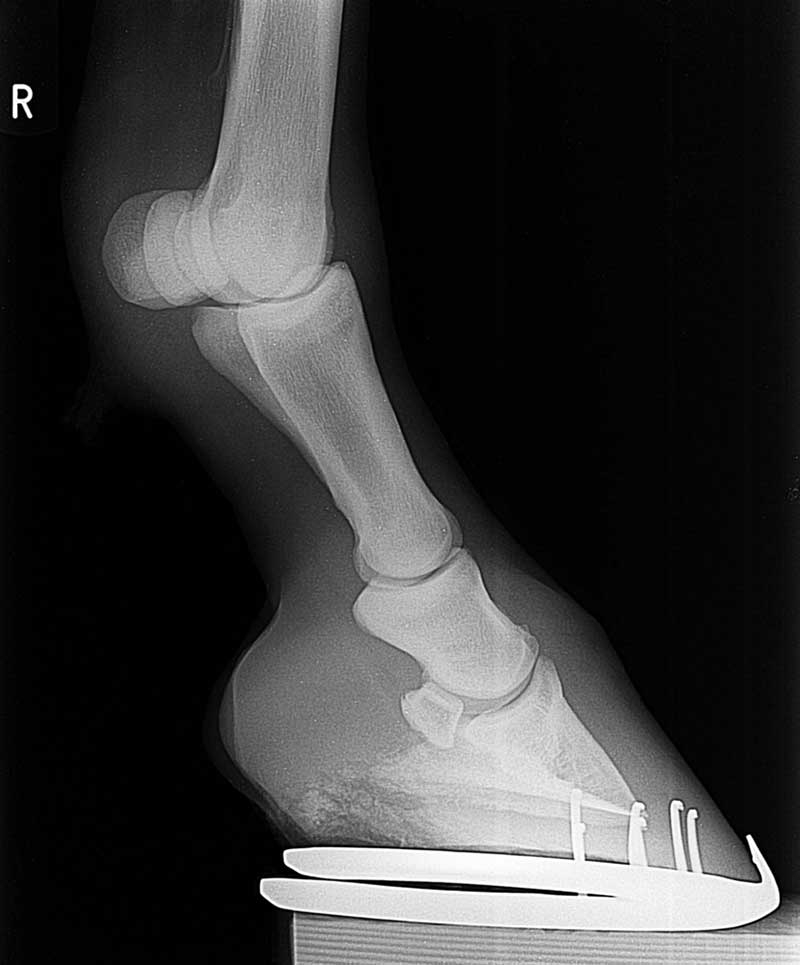

For this reason, we use digital radiology, which is the best way to get quality x-rays quickly and efficiently. Your horse’s digital images are ready almost instantly for us to view. Also, instead of taking film after film to adjust the settings, we can simply adjust the contrast on the computer. This means that we can take fewer films and not expose your horse to as much radiation.

Digital x-rays are great for diagnosing lameness in horses. We can quickly and efficiently diagnose your horse, whether he or she is suffering from laminitis, a broken bone, or anything else.